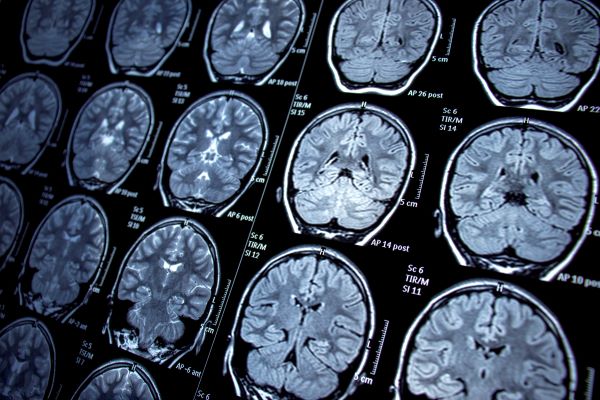

Dementias Platform UK yn lansio hyb delweddu arloesol newydd

Bydd hyb delweddu arloesol, a ddatblygwyd gan dîm porth data Dementias Platform UK yn yr uned gwyddor data poblogaethau ym Mhrifysgol Abertawe, yn galluogi ymchwilwyr i gael mynediad unigryw at sganiau sy’n delweddu’r ymennydd.